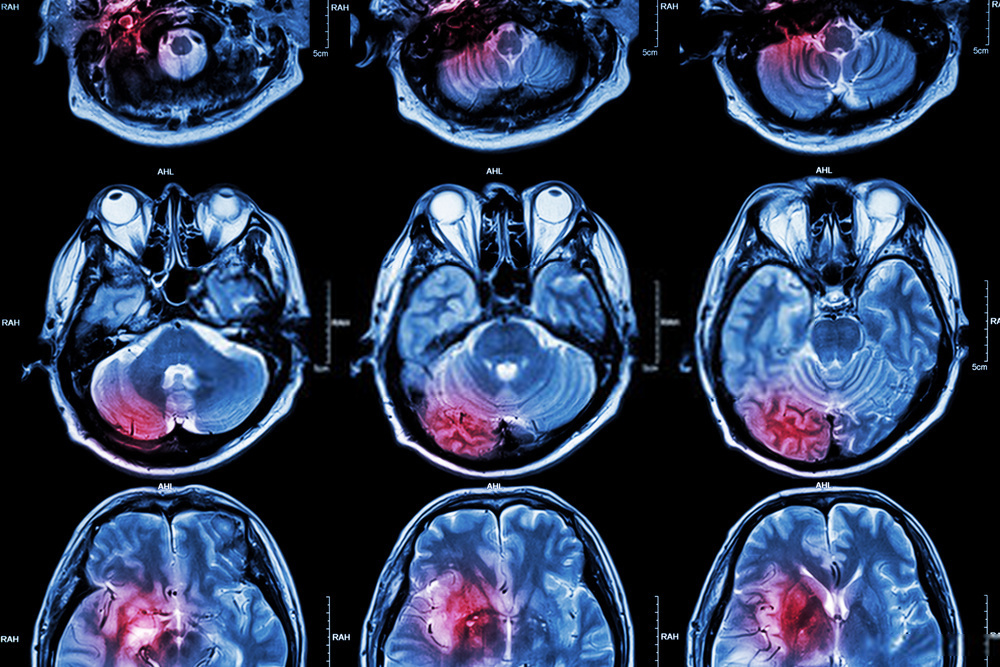

এই একই বিষয়টি নিয়ে পরবর্তীতে আরো বড় পরিসরে গবেষণা করা হয় এবং তারা মোবাইল ব্যবহার করার জন্য Acoustic Neuroma এর সূত্র পায়নি। এর পরবর্তীতে গবেষণা করেছিল বিশ্ব স্বাস্থ্য সংস্থা। তারা গবেষণার পর এটা বলেছিল যে, নিয়মিত মোবাইল ব্যবহার করলে এই টিউমার হবার সম্ভাবনা ১০ শতাংশ বেড়ে যায়। এই Glioma হলো এক ধরনের স্নায়ু কোষ, যার ফলে Malignant brain cancer হয়। কিন্তু এই গবেষণার ও একটি দুর্বল দিক বা ত্রুটি রয়েছে।

তারা এই গবেষণা করার ক্ষেত্রে মানুষের থেকে নেওয়া তথ্যের ভিত্তিতে প্রতিবেদন তৈরি করে। সে কারণে প্রকৃত তথ্য পাওয়ার সম্ভাবনা কমে যায়। এক্ষেত্রে তৃতীয় কোনো পক্ষ যদি কতগুলো ব্যক্তির উপর লক্ষ্য করতো, যে কোন ব্যক্তি কতক্ষণ মোবাইল ব্যবহার করছে এবং সর্বশেষ কতজন আর মধ্যে Glioma সৃষ্টি হয়েছে, তবে এ ক্ষেত্রে সেই গবেষণার ফলাফল করার যোগ্য হতে পারত। অন্য আরেকটি কারণ হচ্ছে Glioma খুবই দুর্লভ একটি ব্রেইন ক্যান্সার। যেটি ১ লক্ষ মানুষের মধ্যে তিনজনার হবার সম্ভাবনা রয়েছে।